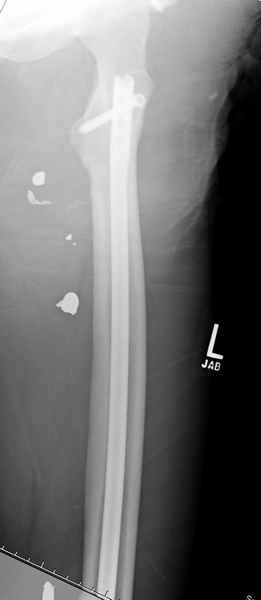

Учитывая, что больной получил травму не во время визита в церковь, и он является одним из представителем 40 миллионного “outstanding itizen”, без медицинской страховки, без работы в свои 39 лет, и без надлежающей ортопедической дисциплины у которого отсутсвует страх стрессового перелома, было рекомендовано оперативное лечение: профилактическое антеградное интрамедуллярное штифтование.

Методика штифтования при отсутствии большой зоны перелома как при онкологических профилактических штифтованиях, расверливание интрамедуллярного канала проводим с предварительным наложением дополнительного дренажного отверстия в дистальном отделе бедра (в данном случаи в канале оставили 6.5 мм канюлированный шуруп), иначе при создании давления в канале во время сверления имеется опасность эмболизации легочной артерии тромбом.